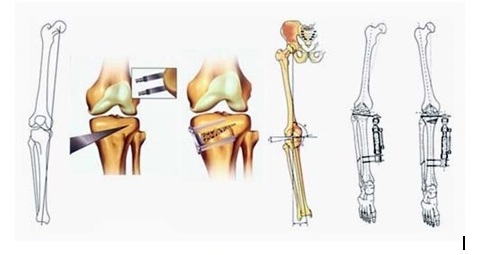

Остеотомії діляться на два типи - кутові (клиновидні і кістковопластичні) і арочні. V -образна остеотомія є їх комбінацією.

Коригувальна остеотомія виконується для виправлення деформацій нижніх кінцівок, прекрасно зарекомендувала себе як методика, яка дає відмінний косметичний результат, а також як альтернатива ендопротезування колінного суглоба.

Корегуюча остеотомія виконується наступним чином: через невеликий розріз частково перетинається (остеотоміюється) великогомілкова кістка в верхній третині або стегнова кістка в нижній третині, виправляється деформація і зона остеотомії фіксується в правильному положенні сучасним фіксатором. Зрощування зони остеотомії, як правило, настає через 10-12 тижнів. Спортивні навантаження можливі через 6 місяців після операції.